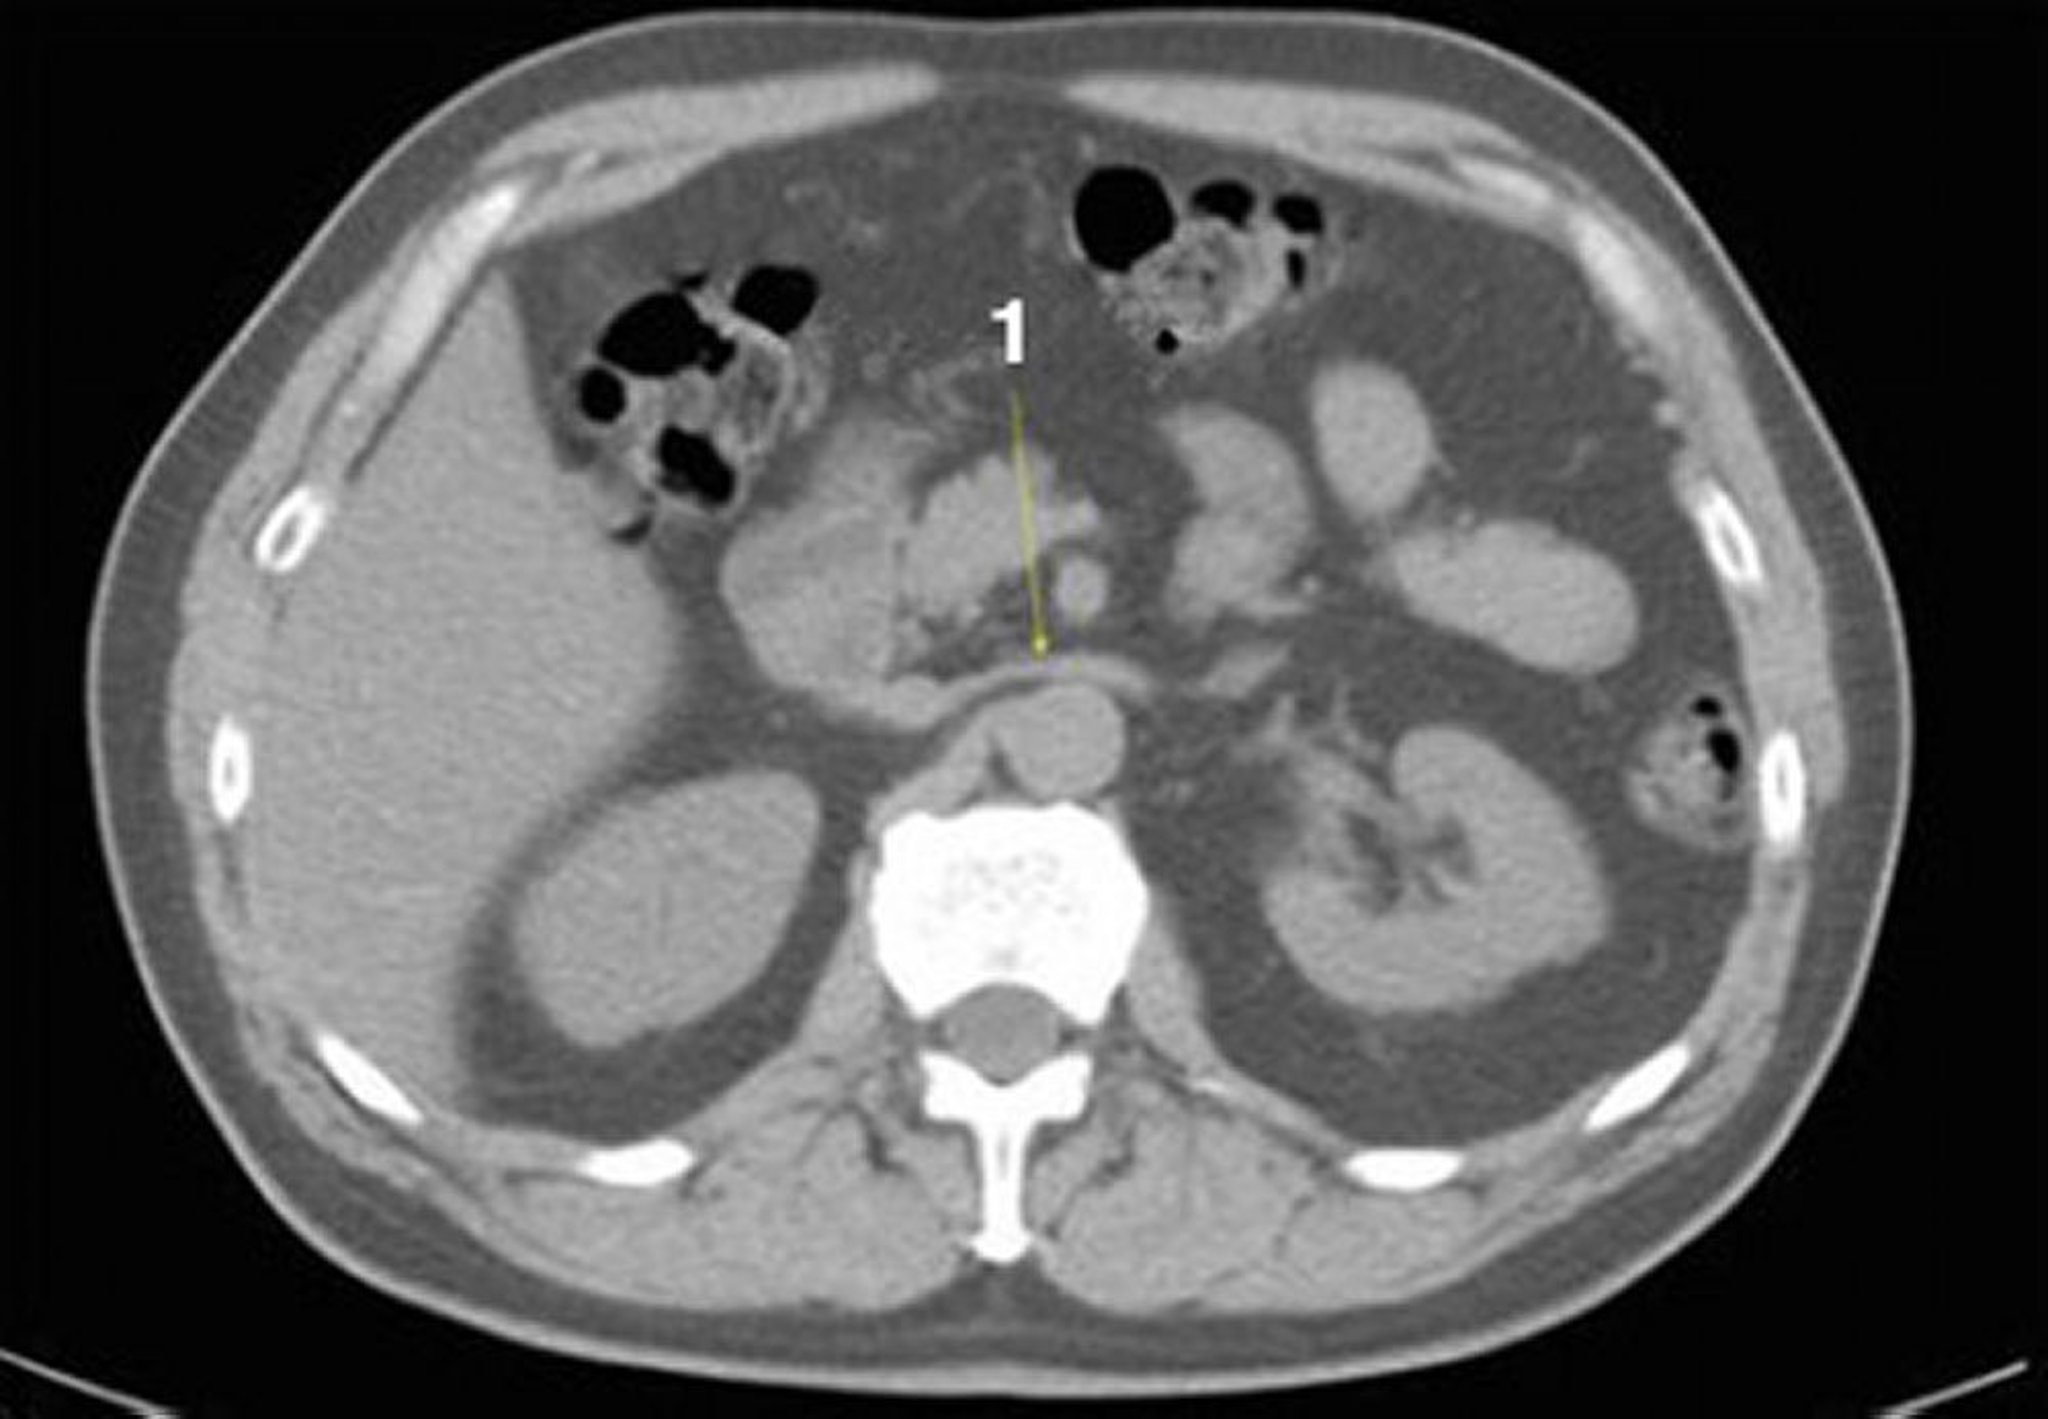

TC senza contrasto dell'addome e della pelvi che mostra un'anatomia normale (Slide 12)

1 = vena renale sinistra.